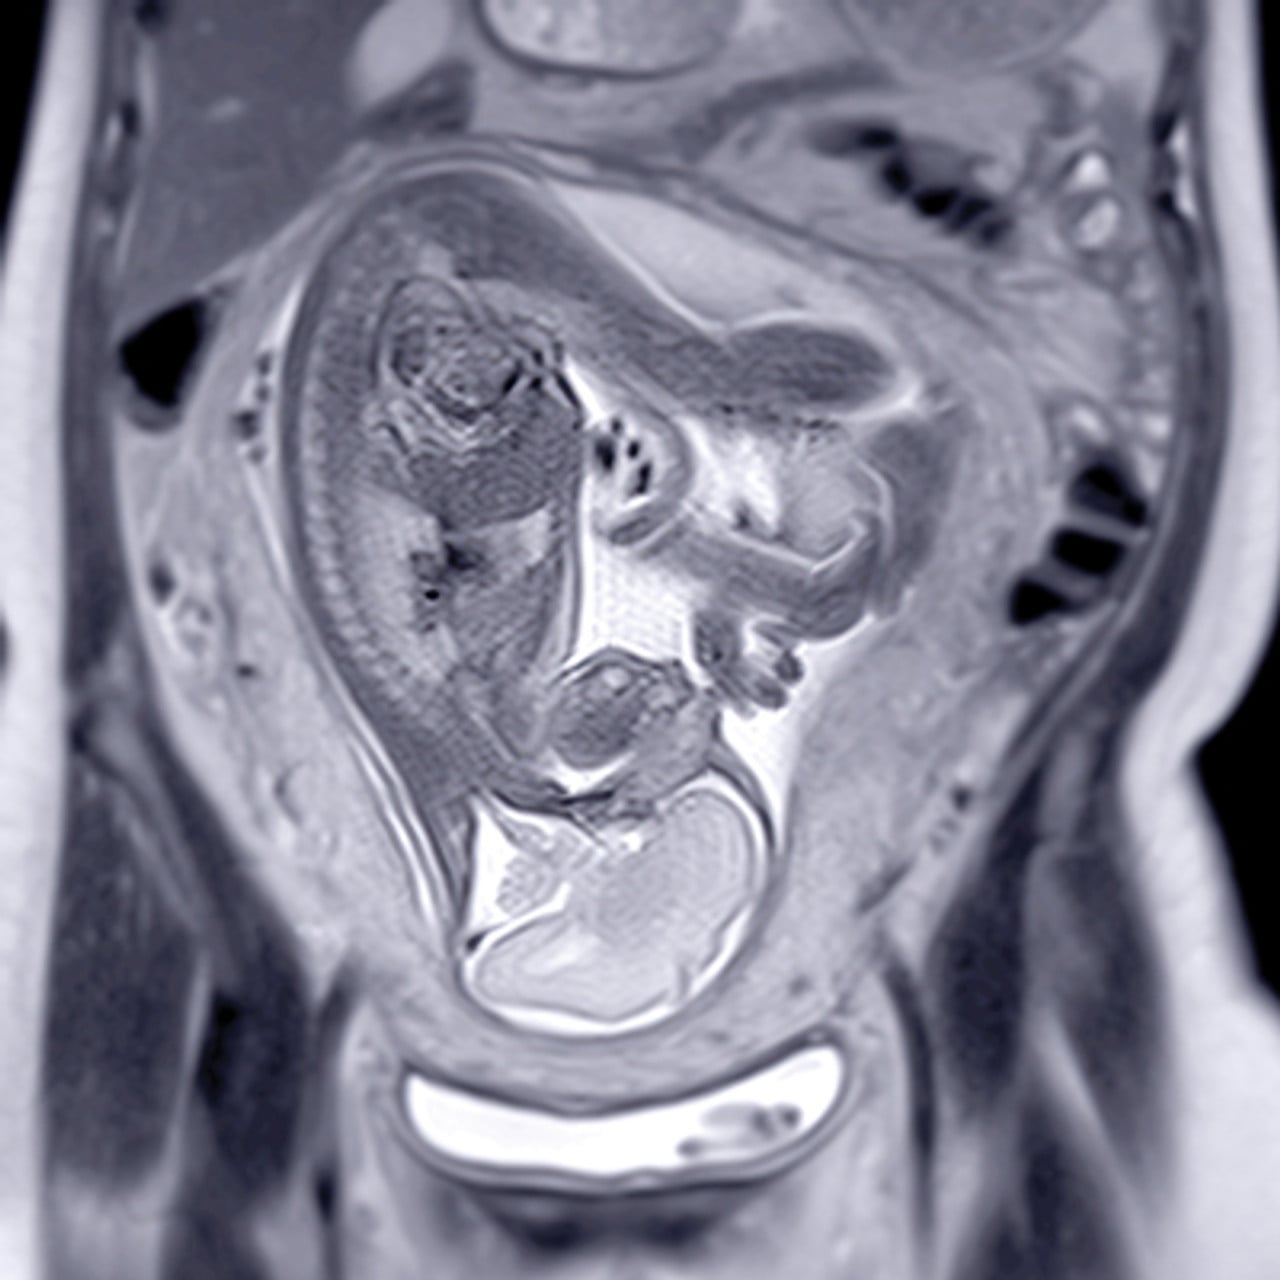

- Identify and recommend treatment for various urgent conditions of the gastrointestinal, genitourinary, and obstetric-gynecologic systems using Ultrasound and CT/MRI